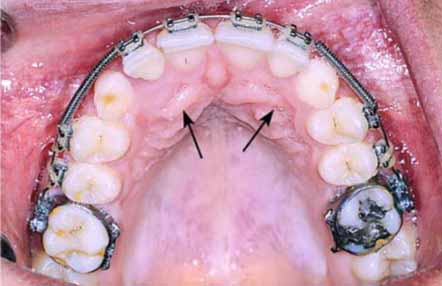

جهت درمان نهفتگی دندان نیش می توان از ارتودنسی ثابت استفاده .کرد در این صورت یک جراحی ساده مورد نیاز است تا دندان نیش نمایان شود. سپس با نصب براکت ارتودنسی روی دندان با زنجیر مینیاتوری به سیم ارتودنسی متصل می شود. پس از مدتی می بایست مجددا نزد پزشک رفت تا توسط بند رابری به ،زنجیر نیروی بیشتری ایجاد کند. با این روند درمان ارتودنسی ناهنجاری دندان نهفته از حالت افقی به عمودی و در جای مناسب هدایت خواهد شد. دوره درمان حدود یک سال به طول می انجامد. در پایان ،درمان بیرون آمدن نهفتگی دندانی را مشاهده خواهید کرد. معمولا این جراحی با بی حسی موضعی صورت می پذیرد. حدود ۴۵ دقیقه جراحی و نصب براکت، به طول می انجامد. اگر هر دو دندان نیش در حالت نهفته قرار داشته باشند، این زمان بیشتر خواهد شد.نمونه ی رادیوگرافی OPG مربوط به دندان نیش نهفته